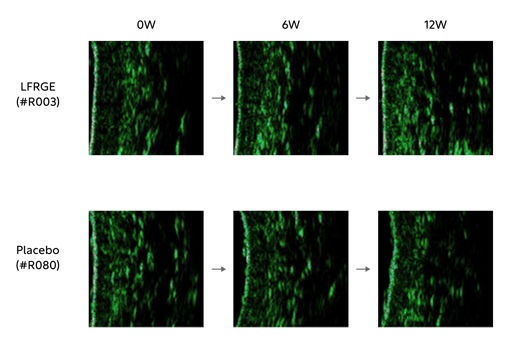

A human clinical trial was conducted with 111 participants over 12 weeks. The test group consumed 500 mg/day of POST SZ075™, and outcomes related to wrinkles and skin condition were objectively measured using instrumental assessments and compared with a placebo group.

In the SZ075 group, the study confirmed improvements in a reduction of crow’s feet wrinkles and an increase in dermal density.

In addition, the skin roughness index also improved, indicating that it helps enhance overall skin texture and condition.

*Key results included:

-Improvement in UV-induced wrinkle parameters

: Up to 1,140% greater reduction in UV-damage–related wrinkle indices versus placebo

: Skin elasticity increased by 614%, skin moisture content by 309%, and dermal density by 172% compared with the placebo group-Improvement in skin hydration and texture

: Significant improvement in skin roughness, indicating benefits for overall skin texture and conditionThrough this clinical study, POST SZ075™ demonstrated its ability to support skin moisturization and help recovery from UV-induced damage. The study was published in Food Science and Biotechnology in 2025.